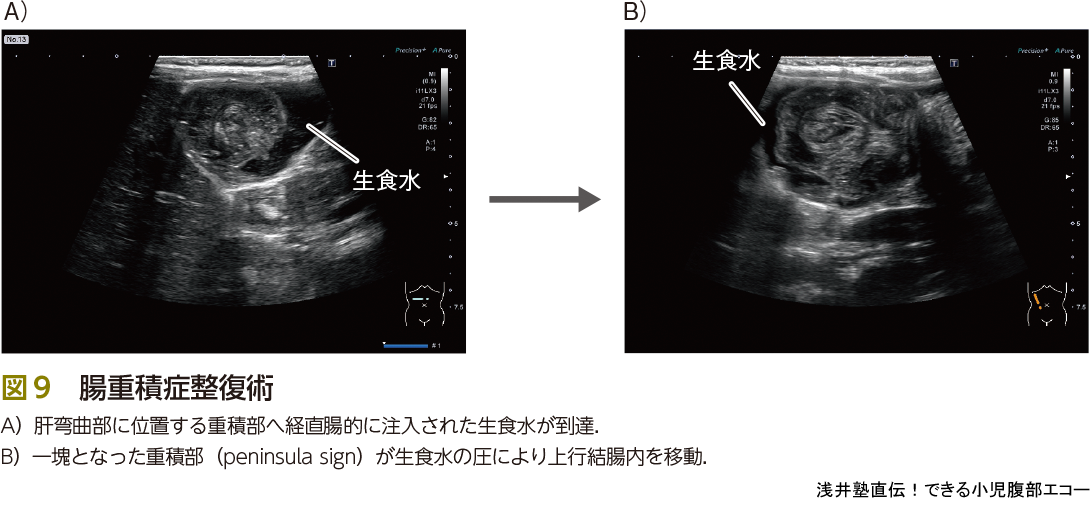

●整復

最後に治療です.腸重積症の診断から治療まですべてエコーで行うことが可能です.診断がついた後,ショックバイタルではなく,エコーで腸管穿孔や壊死の所見などがない場合に整復可能と判断します.また多量の硬便貯留があるかどうかもエコーで確認し,適宜浣腸をかけた後に行います.硬便の存在は整復率を低下させます.

場所は蘇生カート,酸素投与,十分なモニターが可能である救急外来で行います.透視室で急変したらたいへんです.被曝をしないことに加えて,場所を問わない,これもエコー整復のメリットです.静脈路確保の後,エコー担当の医師,鎮静・鎮痛・気道管理を行う医師の2人以上で行います.医師が1人しかいない場合の自家麻酔はリスクが上がるので避けるべきですが,医師が2人以上かつ鎮静スキルを有しているならばできるだけ鎮静・鎮痛を行ってもいいのでは,と考えます.この整復術は非常に苦痛と恐怖を伴います.鎮静をかけると児の状態評価が難しい! と思う方もいるかもしれませんが,整復中の状態悪化は穿孔によるものです.エコーを使用していると,腹水の貯留や生理食塩水の滴下速度をみることで穿孔の有無が即座に判断可能です.また体動もないのでモニタリングが容易ですし,整復率があがる報告もあります.医師のスキルしだいで児に苦痛や恐怖を与えるかどうか? 保護者に大絶叫をきかせてしまうか? 大事な課題です.また,記録や介助のため看護師1~2名も同席します(図8).

さて,整復開始です.整復の手順は下記のとおりです.